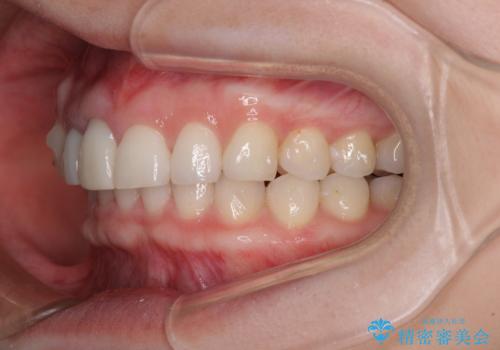

- 一度矯正治療を希望して始めたものの断念し、前歯をセラミッククラウンで治療した後に、やはり矯正でしっかり治したいとのことで来院された患者様です。

当初、前歯の歯列矯正を希望して銀座院に来院され、補助装置を装着するところまで進んだのですが断念してしまいました。

その後、他院で気になる前歯をセラミッククラウンで補綴治療をしたそうですが、やはり歯列を整えたいとのことで再度来院されました。

クラウンの状態は、根管治療の状態も含めて決して良い状態とは言えず、矯正治療後の根管治療と補綴治療の再治療を前提として、インビザラインによる矯正治療を行うこととしました。